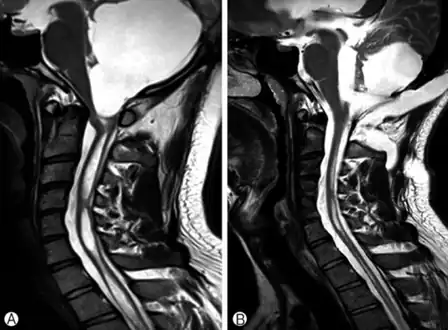

-

a)Large cystic mass at the posterior fossa with compression of the 4th ventricle b) postoperative MRI, a residual cyst and syringomyelia was decreased. -